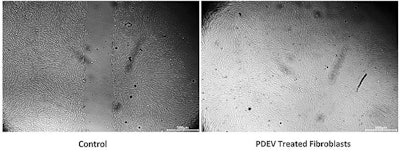

Following research showing Euglena gracilis derived EVs enhanced skin-regenerative wound healing [14], a recent in vitro wound healing study showed human fibroblasts treated for 24 hours with PDEVs, increase their wound healing ability by 52% when compared to untreated wounded fibroblasts (see figure 3, below). The wound healing assay demonstrates the migratory capacity of cells in vitro. In the assay, a wound is made in a monolayer of cells and the rate of wound closure is measured at various time points.

In the experiment shown in figure 3, normal human dermal fibroblasts (NHDF) were grown into continuous compact cell monolayers before wounds were made. The wounded cell monolayers were either treated with PDEVs or left untreated (control). The distance between the two cell fronts in both the PDEV treated and untreated wounds were monitored and compared with the distance when the wounds were first made (time zero). After 24 hours, the cells treated with PDEVs had achieved complete wound closure, while the untreated control cells had only approximately 52% wound closure. This wound assay demonstrated how plant exosomes (PDEVs) can positively influence NHDF cell migration, making plant exosomes excellent candidates for anti-aging products formulated to address fine lines and wrinkles.